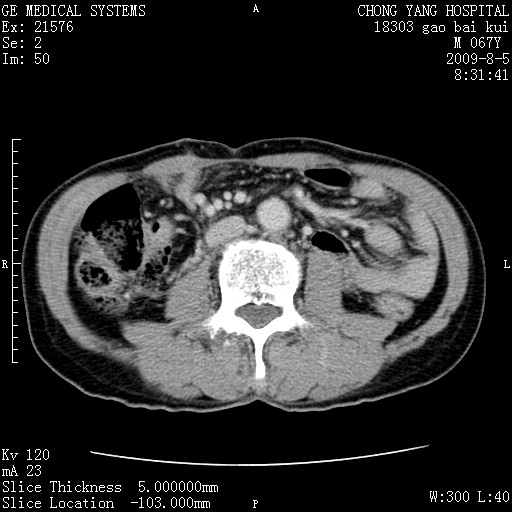

这个也过了,考虑胰腺钩突癌或壶腹癌,不除外胰管粘液乳头瘤伴胰管扩张,肝内胆管积气.

1)考虑胰头癌或壶腹癌并胰管扩张。2)肝外胆管扩张、积气,胆囊影未见;考虑术后改变。3)胃壁增厚?建议必要时行胃镜检查。

考虑胰头癌并十二指肠受侵。